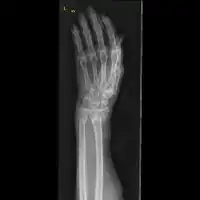

Front view of bowing fractured radius and ulna -

Side view of bowing fractured radius and ulna